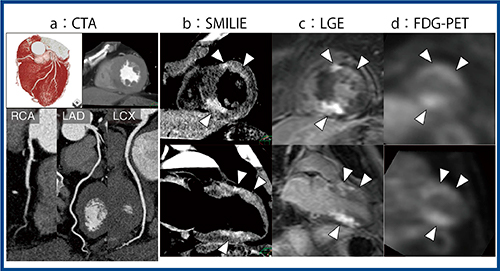

症例3は,心房細動を主訴に狭心症疑いで当施設を受診した(図5) 。冠動脈に問題は認められなかったが,SMILIEでは冠動脈の支配領域とは関係なく,全体に遅延造影効果が散在していることが確認できた(図5 b)。MRIのLGE(図5 c),FDG-PET(図5 d)でも同様の濃染が認められたことから,心サルコイドーシスが疑われた。

当施設で経験した心サルコイドーシス疑いの症例について,SMILIEとMRIのLGEで検出能を比較した結果をRSNA 2018で報告した。11例176セグメントで検討したところ,LGEの集積部位はすべて,SMILIEでも認められた。一方で,SMILIEのみで検出された部位が6セグメント認められた。これは,CTの空間分解能の高さが影響したと考えられた。

図5 症例3:狭心症疑い(サルコイドーシスと診断)

(RSNA 2018で発表)